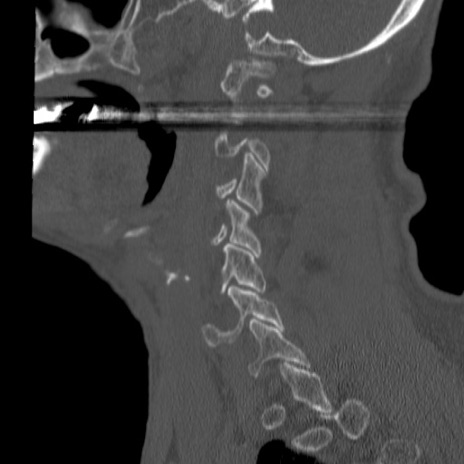

症例46 頚椎CT(矢状断像)

【症例】80歳代男性

【主訴】両側頚部〜上肢のしびれ

【現病歴】昨日、自宅内で転倒、その後より上記症状あり。意識障害なし。

【身体所見】両側上肢のallodynia(熱痛覚過敏)あり。MMTおよびDTRは正確な所見取れず。両上肢の挙上はなんとか可能。

異常所見と診断は?